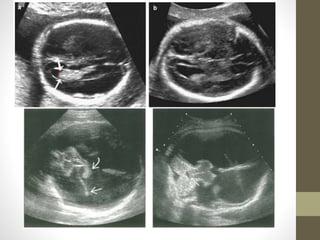

AGENESIS OF CORPUSCALLOSUM (ACC) โ€ข The normal development of the corpus callosum begins anterior (genu) and progresses to posterior (splenium). Agenesis may be partial (affects dysgenesis posterior aspects) or complete. โ€ข US Features โ€ข The corpus callosum is not visible in complete agenesis. โ€ข โ€ข Colpocephaly โ€ข โ€ข Lateral ventricles are displaced laterally (parallel lateral ventricles). โ€ข โ€ข Enlarged 3rd ventricle expands superiorly (high riding third ventricle). โ€ข โ€ข Angulated frontal horns (coronal view)( U or VIKING HORN CONFIGURATION) โ€ข โ€ข Abnormal (sunburst) gyral pattern in interhemispheric fissure is a late feature. โ€ข โ€ข The presence of a cavum septum pellucidum excludes complete Agenesis

• 48.

โ€ข Common associationsinclude: โ€ข Dandy-Walker (DW) syndrome โ€ข Holoprosencephaly โ€ข Heterotopias โ€ข โ€ข TVS scaning is often helpful for early diagnosis. โ€ข โ€ข Associated with pericallosa llipoma (hyperechoic)